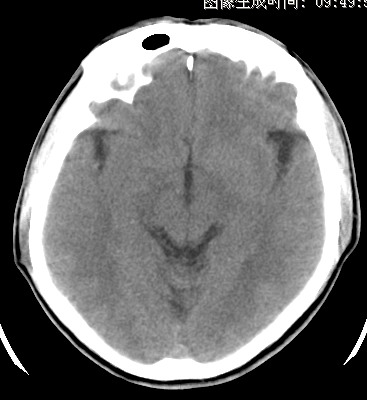

标题: CT17787:头ct,请帮忙看看右顶部有无异常 [打印本页]

男,58岁,偶有头疼

未见明显异常。右顶部低密度影为深入的脑沟。

增宽的脑沟!无异常!

是宽大的脑沟,局部不象有萎缩现象

增宽的脑沟

诊断依据:

低密度影周围脑组织边缘均有一层脑灰质覆盖。

正常啊,是对右顶增宽脑沟有疑问吗